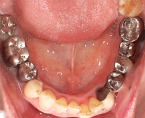

保険適用で奥歯のむし歯治療を行なう場合は、金銀パラジウム合金(通称:金パラ)と呼ばれる銀色の詰め物・被せ物を行います。

保険は適用されませんが、白いセラミックで出来た詰め物・被せものを使用することで、天然の歯のように見える、自然で清潔感溢れる笑顔を取り戻すことができます。歯の適合もより良いため、二次むし歯や歯肉炎になりにくいといったメリットもあります。

また、セラミックの場合は金属を使わないため、金属アレルギーの心配がなく、歯ぐきが黒ずむことも少なくなります。(審美歯科)